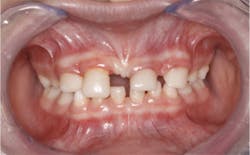

A nine-year-old female was referred to me by a local pediatric dentist (figure 1). The pediatric dentist felt she had reached the limit in what she could provide for the patient cosmetically. The patient had received only routine dental care and cosmetic bonding thus far. She was entering fourth grade in school and was becoming increasingly self-conscious about her smile (figure 2).

Upon clinical and radiographic examination, the patient presented with multiple missing permanent teeth (figures 3, 4a, and 4b). Tooth No. 8 was malpositioned and slightly mobile. Her mandibular dentition was stable and intact, although mostly deciduous (figure 5). Upon further questioning, I learned that her brother had a similar condition. Taking into consideration the patient’s physical appearance and the genetic similarity to her brother, I discussed with her parents the need to obtain a medical diagnosis through genetic testing.